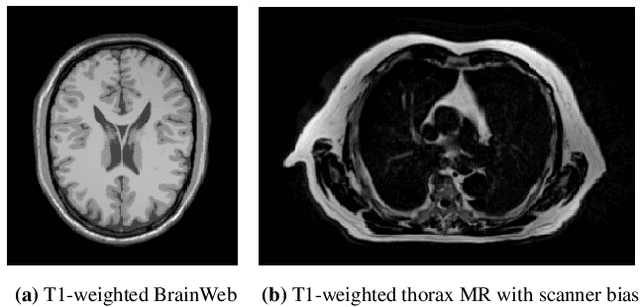

Abstract:A spatially regularized Gaussian mixture model, LapGM, is proposed for the bias field correction and magnetic resonance normalization problem. The proposed spatial regularizer gives practitioners fine-tuned control between balancing bias field removal and preserving image contrast preservation for multi-sequence, magnetic resonance images. The fitted Gaussian parameters of LapGM serve as control values which can be used to normalize image intensities across different patient scans. LapGM is compared to well-known debiasing algorithm N4ITK in both the single and multi-sequence setting. As a normalization procedure, LapGM is compared to known techniques such as: max normalization, Z-score normalization, and a water-masked region-of-interest normalization. Lastly a CUDA-accelerated Python package $\texttt{lapgm}$ is provided from the authors for use.